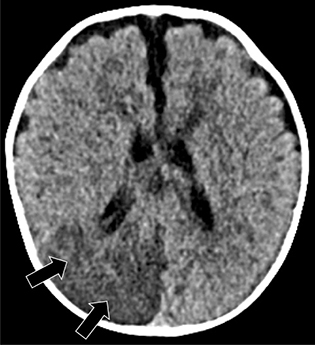

Although CT is often the first imaging modality performed, MR is generally preferred for its greater sensitivity, specificity, tissue contrast, and non-reliance on ionizing radiation or, in most cases, exogenous contrast agents. CT is nevertheless sensitive for acute intracranial hemorrhage in the acute setting. Cerebral infarction in the neonate has a similar appearance to that in the older child or adults, manifesting as a well-defined region of hypoattenuation in an arterial distribution (Figure 4), although small lesions can be difficult to identify on routine imaging due in part to unmyelinated brain masking subtle hypoattenuation. Additionally, certain areas in the posterior temporal and occipital cortices can have low attenuation on CT in normal infants and the risk for false positive classification of stroke merits circumspection. The “hyperdense artery sign” representing acute intraluminal thrombus is infrequently observed in neonates, and may relate to varying clot compositions, including potential differences in the presence, concentration, or composition of red blood cells and iron within the heme moiety of hemoglobin (45).

Fig 4

Figure 4. A 14-day-old boy with seizures. Axial non-contrast CT image showing unilateral diffuse hypodensity in the right PCA distribution (arrows). Case courtesy of Dr. Tamara Feygin, Department of Radiology, Children’s Hospital of Philadelphia.